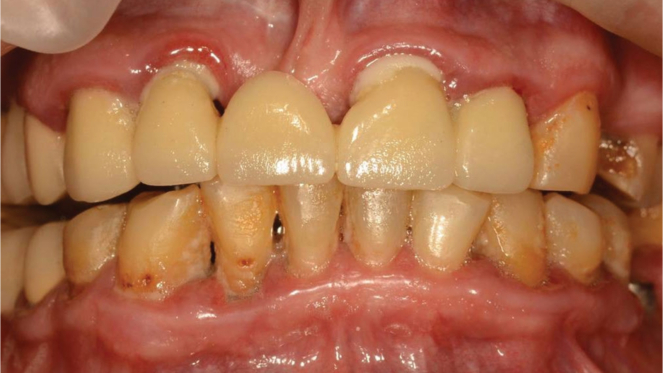

Пародонтит тяжелой степени

Результат через 2 недели

Параметры изменяются в зависимости от процедуры

Хронический пародонтит средней степени тяжести

Вектор терапия по схеме, затем ФДТ 2-3 раза в неделю Сочетание периоскан, вектор-терапии и ФДТ 2-3 раза через неделю.

Гингивит и легкая степень пародонтита

Результат спустя неделю